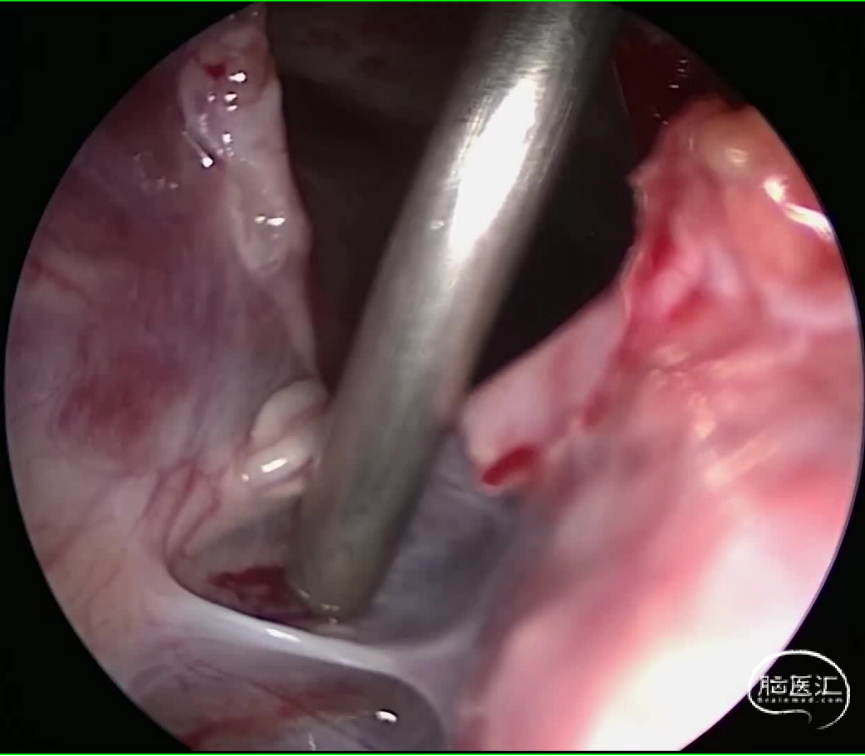

中山大学肿瘤防治中心影像医学中心的刘海彬医师为患者手术提供了高质量的影像学资料,为制定手术方案提供了很大的帮助。完善相关检查,经由神经外科脊髓脊柱亚专业组MDT讨论,萧女士的T11-L3椎管内硬膜间占位行囊腔探查术+漏口修补术。电生理监测,根据术前影像学可大致定位漏口位于L1水平,单个椎板暴露,术中用角度内镜探查确认漏口位置,避免过度牵拉脊髓及神经根,避免加重神经功能障碍,维护脊柱稳定性,是该手术的目标。张继教授阅片后指出:T11-L3椎管内病灶,考虑硬脊膜囊肿可能性大,单个椎板暴露,双镜联合下探查漏口位置,实现预定手术目标(自体组织修补漏口,缓解术前症状),为神经功能恢复创造条件。避免已经变薄硬脊膜和蛛网膜破损,减少了蛛网膜下腔血性脑脊液刺激的概率。

图2 手术过程: 病灶位于硬脊膜夹层见,见清亮脑脊液,有多个分隔,内镜下探查并开通数个分隔,漏口位于L1水平,以自体组织进行修补交通口。